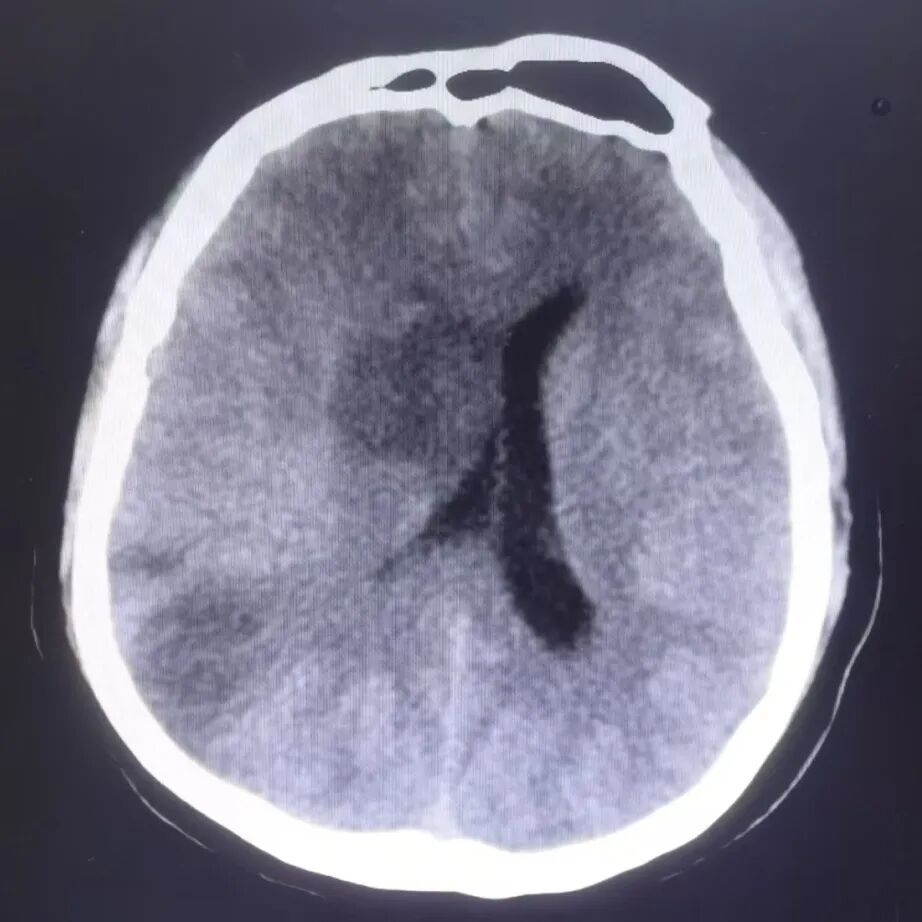

并发症处理:术后24小时患者精神状态差,意识模糊,查体昏睡,双侧瞳孔不等大,左侧直径3mm,右侧直径5mm,无光反应,左侧肢体肌力Ⅳ级,复查头颅CT水肿较重,请神经外科会诊,急诊行去骨瓣减压术。

动脉长鞘怎么置入有励可说|Locaste 088励楷长鞘在右侧颈内动脉闭塞并夹层术中的应用_https://www.jmylbn.com_新闻资讯_第18张